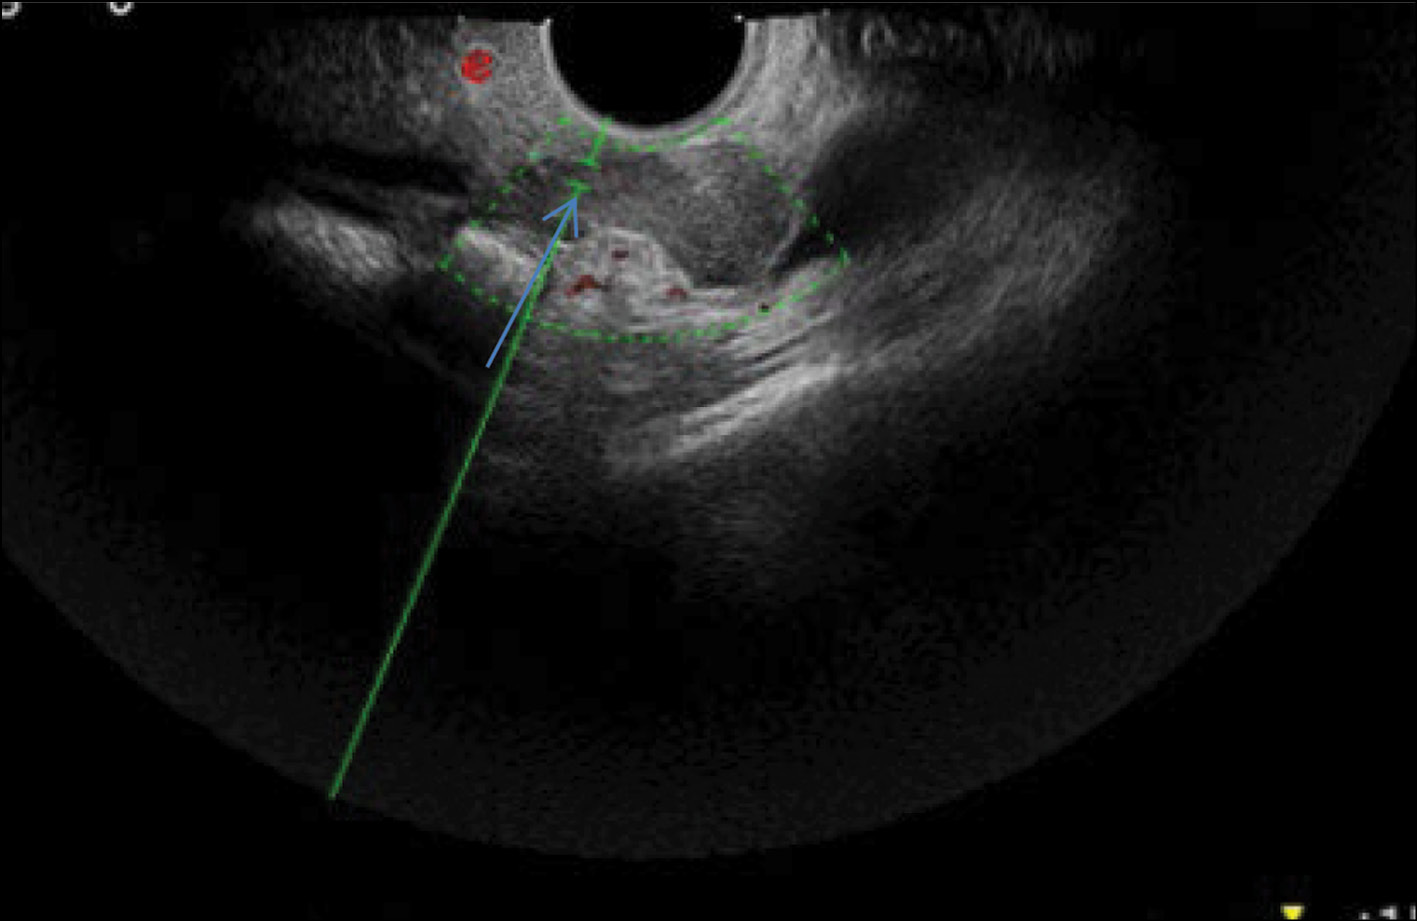

After diagnostic laparoscopy and biopsy of lesions in the pelvic peritoneum performed in another medical institution, complex ultrasonography was performed at the RRCR. An inhomogeneous isohypoechoic mass with areas of an anechoic structure of irregular and rounded shape was found in the projection of the right appendages. Pronounced pathological blood flow in the solid component of the mass, ascites, and carcinomatosis of the peritoneum of the small pelvis were also found. Figure 1 shows a 3D angiogram of the primary malignant struma ovarii on the right ovary.

Fig. 1. 3D angiography of a poorly differentiated malignant struma ovarii on the right (arrows).

eSaote Pro machine US was used; the transvaginal transducer and volume transvaginal transducer were used. Ultrasonography was performed in a standard 2D mode, and high-tech US methods were then used: power Doppler mapping, US computed tomography (CT), and 3D angiography.